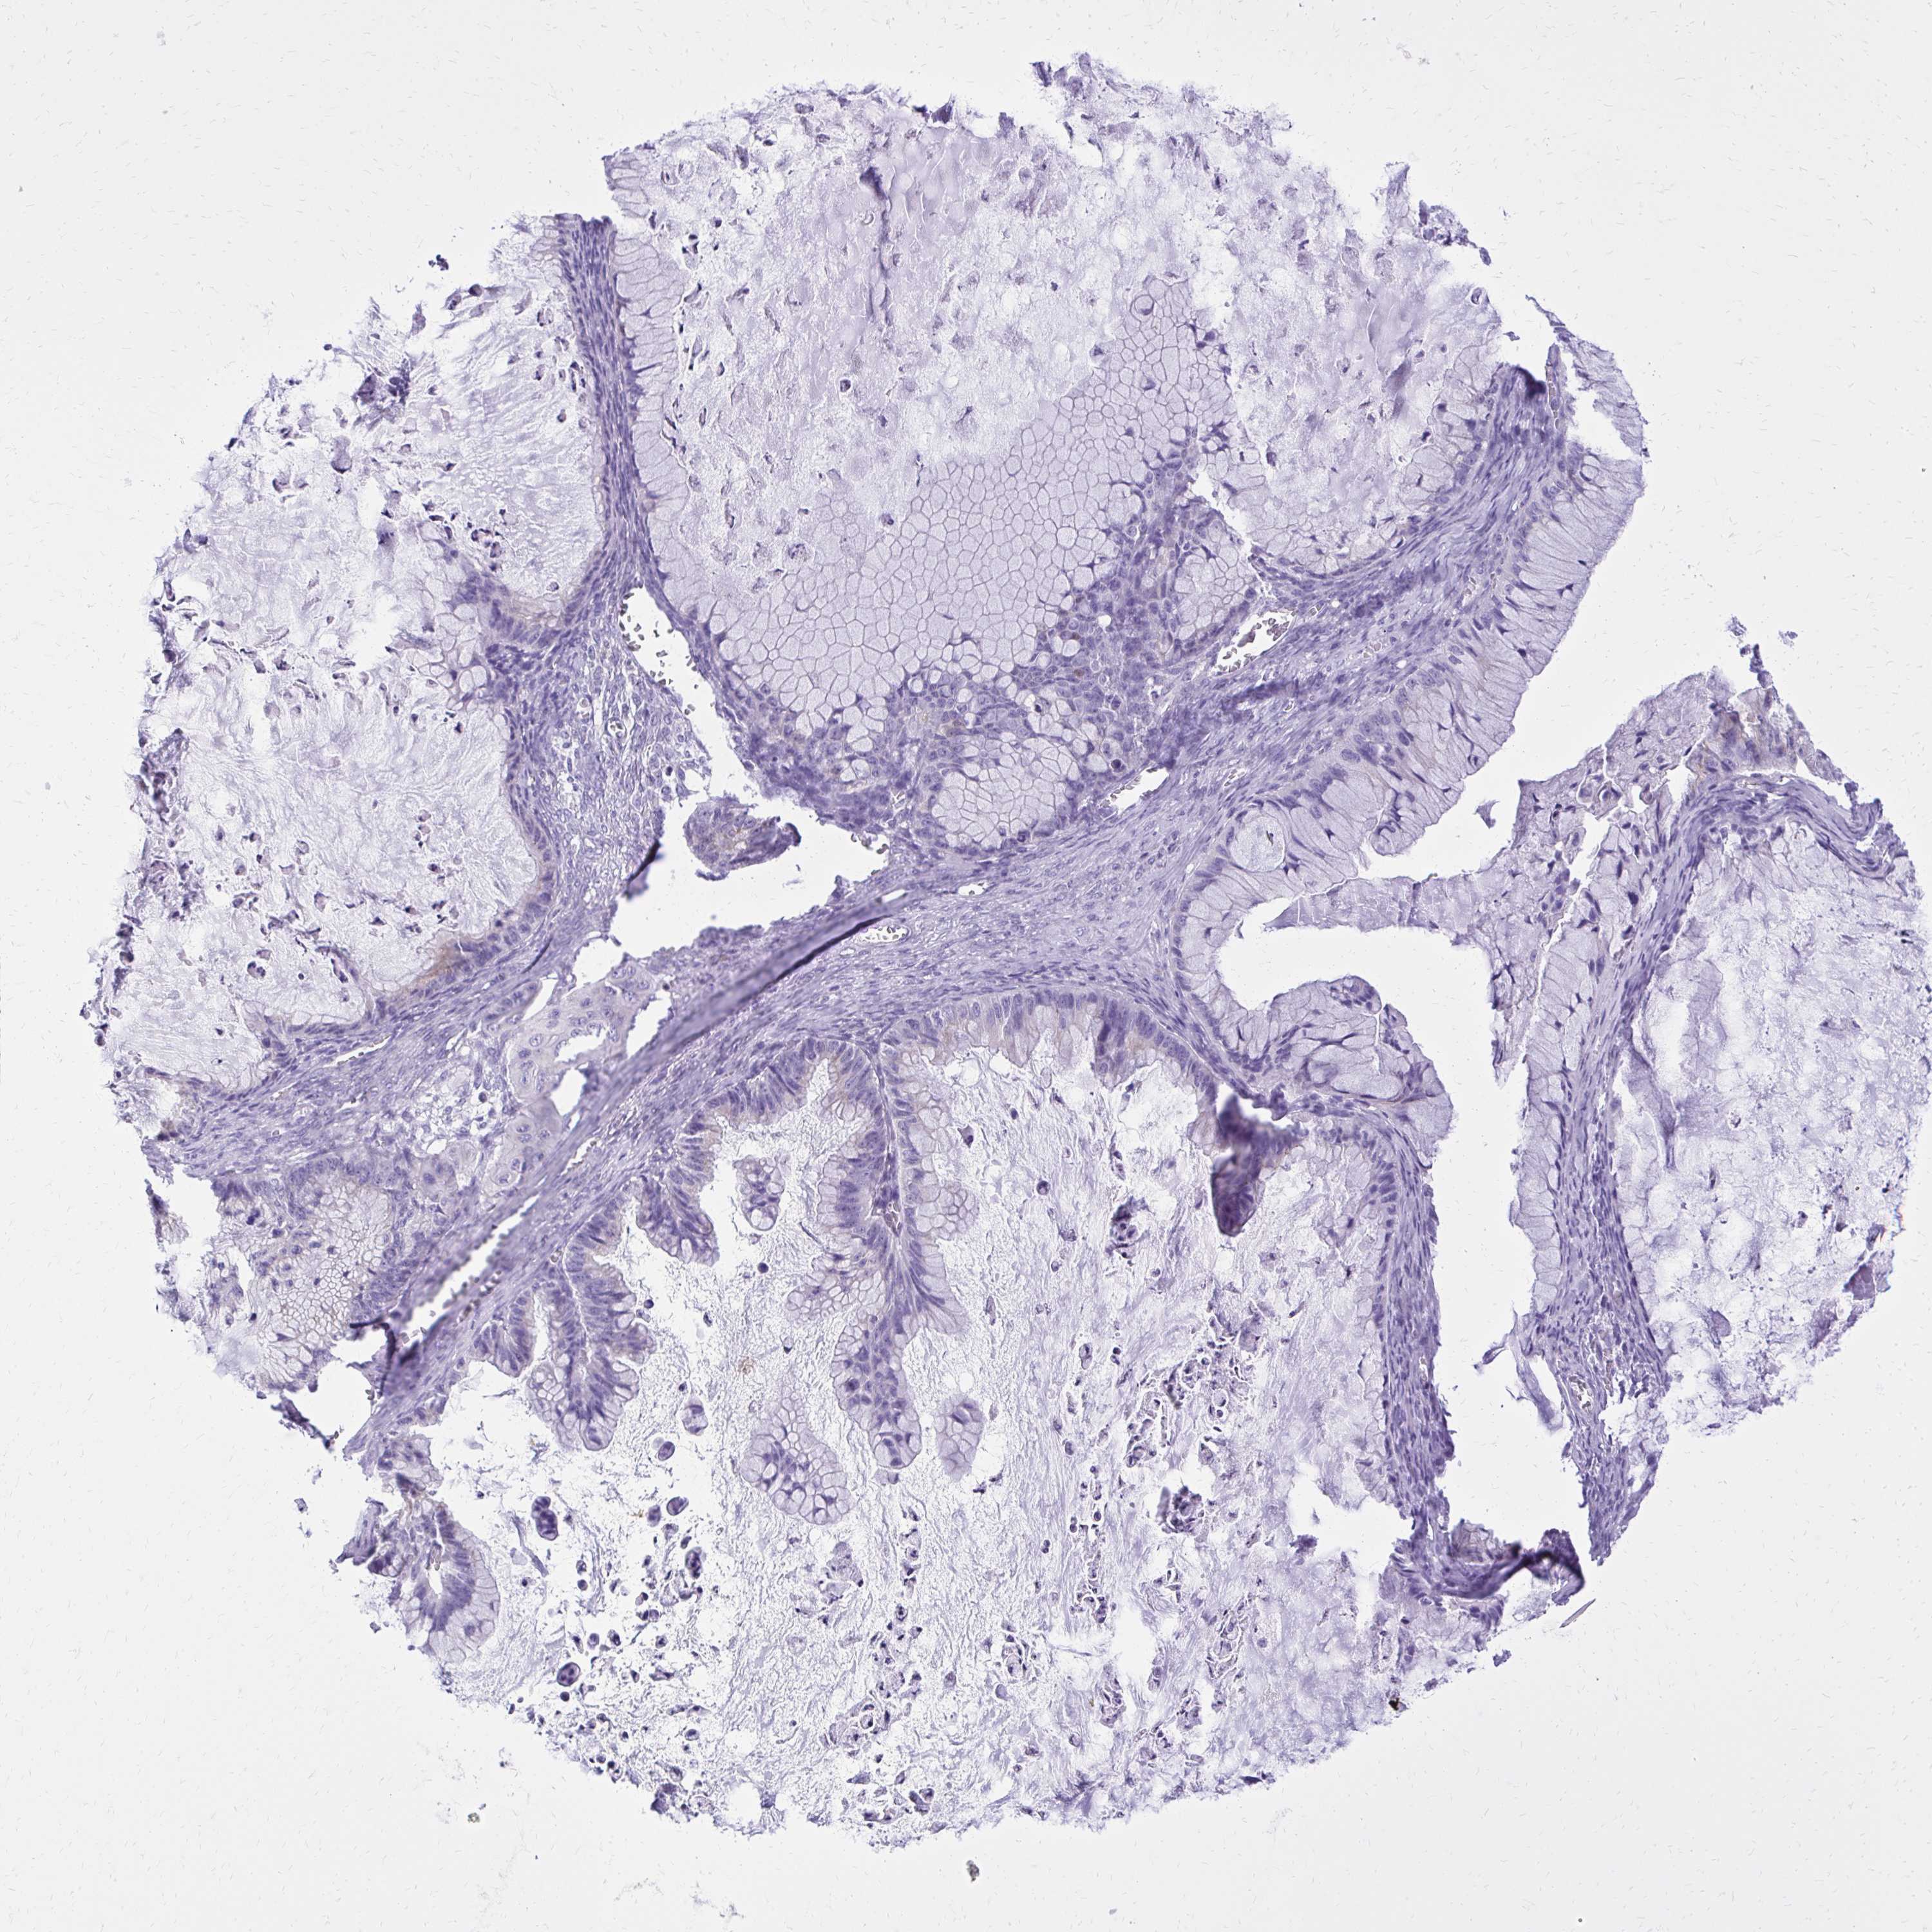

OVARIAN CANCER - Protein expressioni

A mouse-over function shows sample information and annotation data. Click on an image to view it in a full screen mode. Samples can be filtered based on level of antibody staining by selecting one or several of the following categories: high, medium, low and not detected. The assay and annotation is described here.

Note that samples used for immunohistochemistry by the Human Protein Atlas do not correspond to samples in the TCGA dataset.

Antibody stainingi

Antibody staining in the annotated cell types in the current human tissue is reported as not detected, low, medium, or high, based on conventional immunohistochemistry profiling in selected tissues. This score is based on the combination of the staining intensity and fraction of stained cells.

Each image is clickable and will lead to virtual microscopy that enables deeper exploration of all samples and also displays staining intensity scores, fraction scores and subcellular localization as well as patient and tissue information for each sample.

Antibody CAB001515

Carcinoma, endometroid